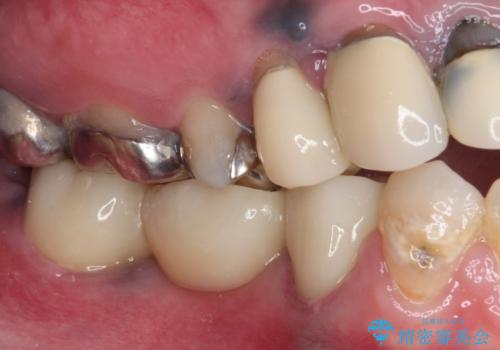

根管治療実施後は速やかに痛みが引き、仮歯で食事を取っても痛むことはなくなりました。

親知らずもむし歯が進行していたため、抜歯をし、傷の治りを待ってブリッジによる補綴治療を行いました。